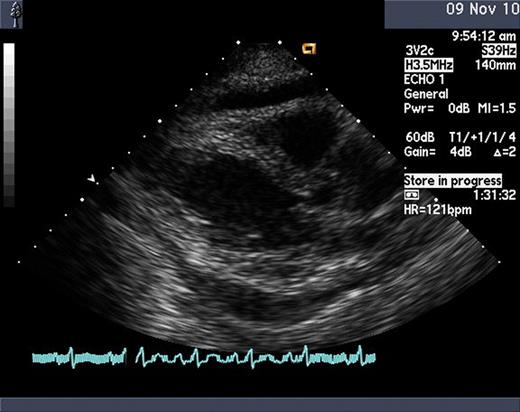

A 69 year old woman with a history of well controlled hypertension and a single episode of viral pericarditis initially presented to her physician with persistent leukocytosis and anemia. Bone marrow biopsy and aspiration revealed acute monocytic leukemia (FAB M5b) with normal cytogenetics. Induction chemotherapy was given with idarubicin 12 mg/m2 for 3 days and continous infusion cytarabine 200 mg/m2 for 7 days. Repeat bone marrow biopsy and aspiration on day 14 showed complete remission. Consolidation chemotherapy was administered with idarubicin 12 mg/m2 for 2 days and continuous infusion cytarabine 100 mg/m2 for 5 days. Prior to discharge from the hospital, she developed sudden onset of substernal chest pain associated with tachycardia and shortness of breath. Physical exam did not reveal jugular-venous distension; however, a slight friction rub was auscultated. Development of a pericardial effusion was suspected. Chest roenterogram demonstrated a mildly enlarged cardiac silhouette with a small left pleural effusion. Serum troponin-I and beta natriutretic peptide levels were within normal limits. Transthoracic echocardiogram was performed immediately which showed a moderate pericardial effusion with right ventricular collapse consistent with pericardial tamponade. A pericardial drain was placed which drained 900 cc of serous fluid. Laboratory studies on the fluid showed WBC of 6,500, LDH 1069, glucose 93, RBC 150, total protein of 4.1, albumin of 2.1 and pH of 7.0. Cultures did not yield bacterial or viral growth. Cytological analysis did not reveal evidence of leukemia. Based on these findings, a diagnosis of cytarabine induced pericardial effusion was strongly suspected.

The patient improved rapidly and within 24 hours, pericardial drain was removed and a repeat TTE showed complete resolution of the pericardial effusion. Repeat bone marrow biopsy and aspiration after consolidation chemotherapy continued to show complete remission. Given that her effusion was likely cytarabine induced, the decision to discontinue further consolidation chemotherapy with cytarabine was made. Instead, maintenance therapy with azacytidine at 50 mg/m2 intravenously daily for 5 days to be repeated every four to six weeks was initiated. After five cycles, surveillance bone marrow biopsy and aspiration has continued to show complete remission. Of the known cardiac toxicities associated with chemotherapy drugs, pericarditis and pericardial effusion are uncommon. They have been reported in association with high dose cyclophosphamide, bleomycin, cytarabine, busulphan, imatinib and all trans retinoic acid. Specifically, capillary leak syndrome, non cardiogenic pulmonary edema and pericardial effusion have been reported with high dose cytarabine. This is the first case of a concurrent pericardial effusion with tamponade with cytarabine evolving so rapidly. The pathophysiology regarding the development of pericardial effusion in this setting is unknown. It has been speculated that direct cellular damage occurs leading to a cascade of events developing eventually into an effusion as well as an immune mediated delayed hypersensitivity. Elevated levels of tumor necrosis factor and platelet activating factor in two patients who developed a capillary leak syndrome after high dose cytarabine therapy have been reported. The strongest theory of a delayed immune mediated mechanism is most accepted given the development of pericardial effusions have been documented after multiple doses of chemotherapy.